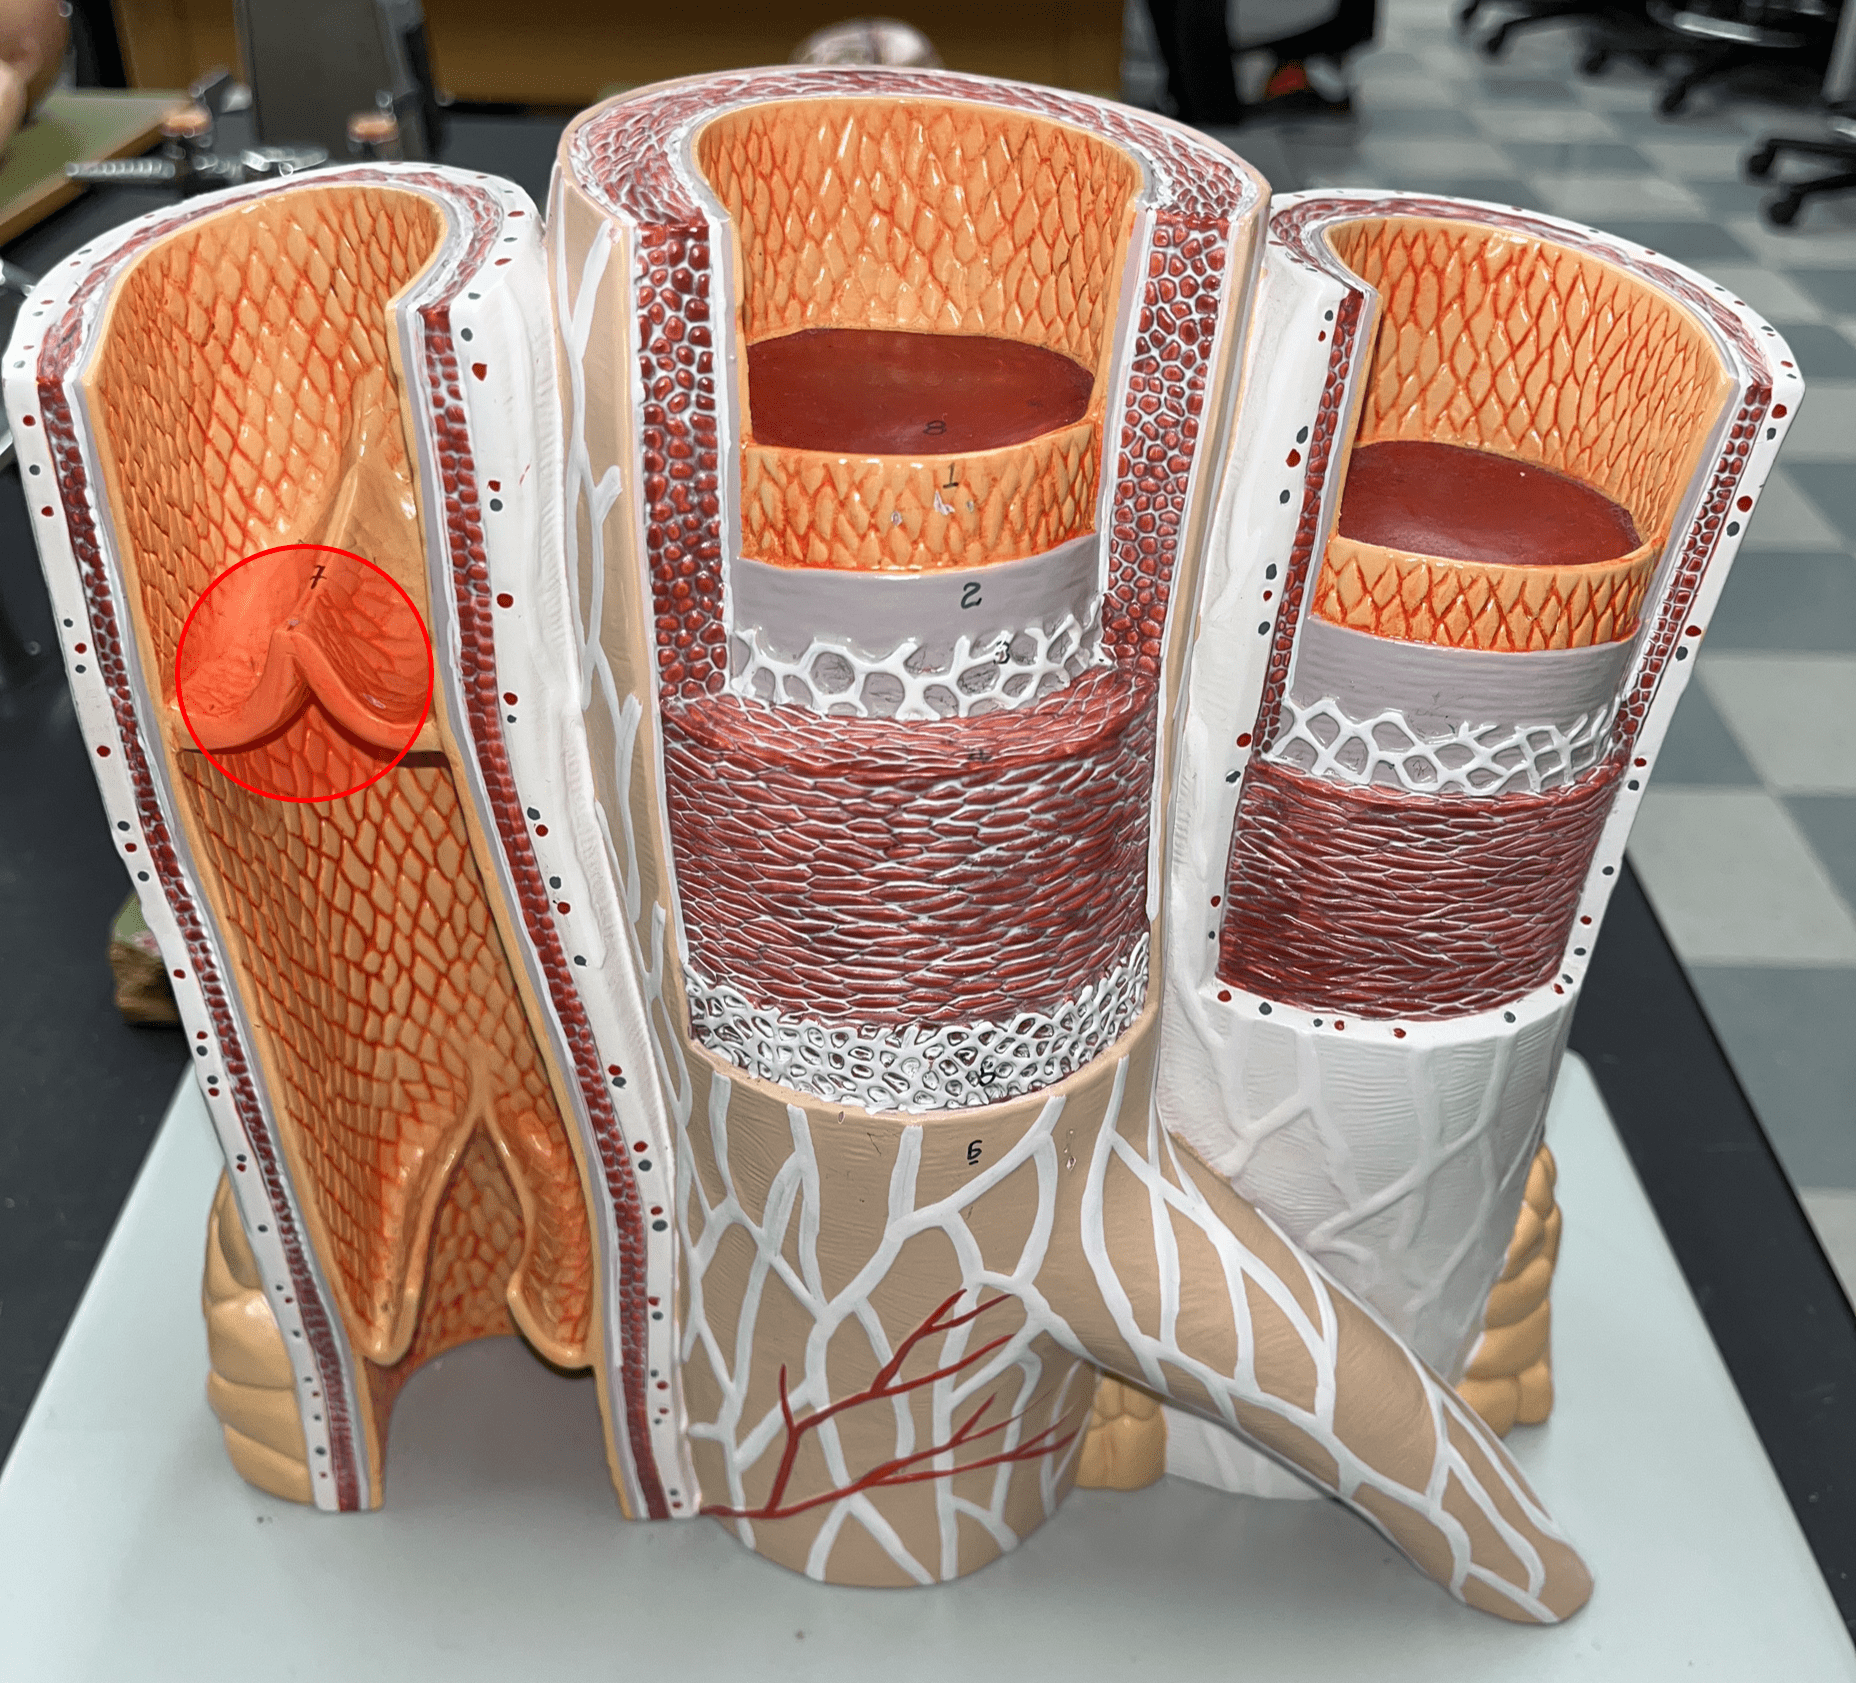

valve

vein

• Some contain valves.